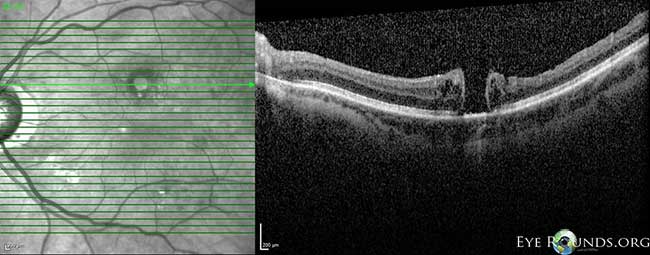

Fig 3-8: OCT OS: scant ERM remnants nasal to the fovea; thinning temporal in areas of prior membrane peeling.